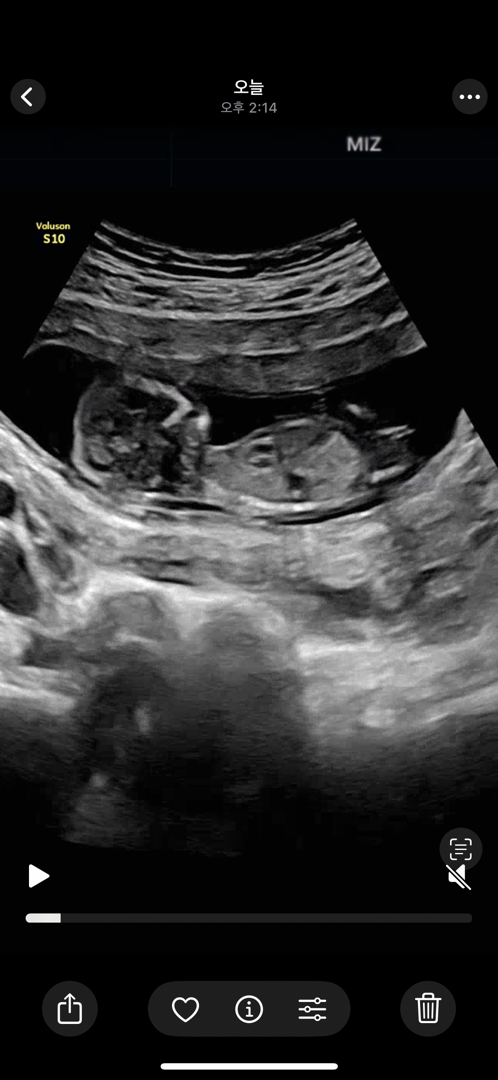

각도법...🌶️🍑

첫째 아들을 키우고 있는 예비 애둘맘이에요:-) 저는 형제맘을 원하고, 남편은 상관없다고 하지만 내심 딸을 바라고 있는거같아서 각도법 지겨우시겠지만 조심스레 올려보아요😭 다른 분들 초음파보고는 아들일거같다, 딸일거같다 보이는데 왜 정작 제꺼는 아리송해보이는지..ㅠㅠ

우왓 감사해요...! 저도 느낌이 뭔가 딸인거같았는데 초음파볼때 하도 가만히 있질않아서 각도 보기가 힘들었어요...

딸같아보여요!!!